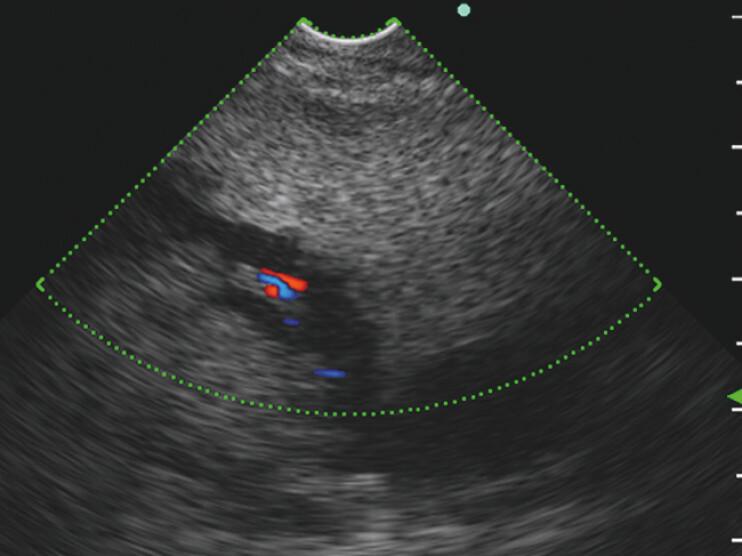

Forward-viewing echoendoscope provides single sessional three biliary drainage routes in a patient with pancreatoduodenectomy.

Endoscopy. 2025 Dec;57(S 01):E333-E334. doi: 10.1055/a-2589-0610. Epub 2025 Apr 29.

Forward-viewing echoendoscope provides single sessional three biliary drainage routes in a patient with pancreatoduodenectomy.前视超声内镜为一名胰十二指肠切除术患者提供了单次 session 的三条胆管引流途径。 (注:这里的“session”在医学语境中可能有特定含义,但仅根据给定文本较难准确意译,直接保留英文更合适些,整体译文可能需结合更多背景信息完善。)